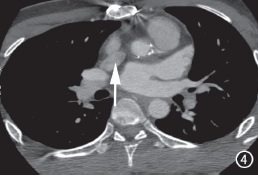

图4 主动脉瓣上管壁钙化,管径小于同水平降主动脉(箭)。